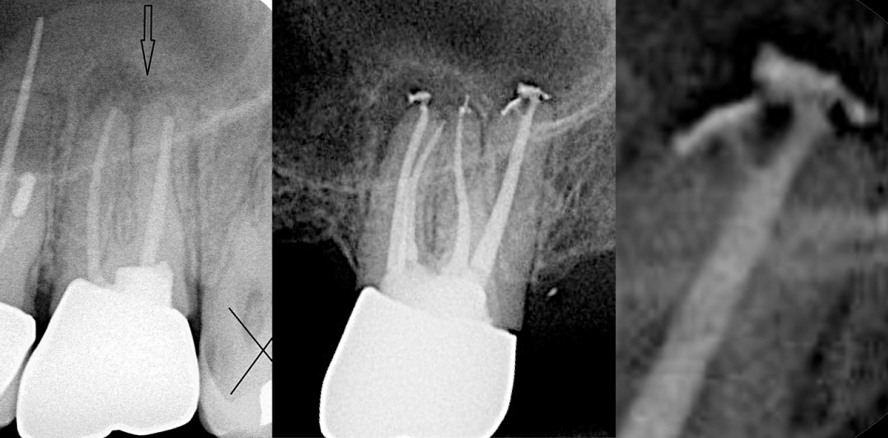

Abramovitz und andere waren die ersten, die die Verwendung der Scheuerbewegung der SAF für die Entfernung derartiger Wurzelfüllungsrückstände vorschlugen.53 Sie präparierten gekrümmte Kanäle in mesialen Wurzeln der unteren Molaren mit Feilen bis zu einer ISO-Größe von 40 und obturierten dann die Kanäle mit Guttapercha und AH 26 mittels lateraler Kompaktion (Abb. 28a). Nachdem der Sealer vollständig ausgehärtet war, wurde eine Revisionsbehandlung durchgeführt. Diese wurde mit Pro-Taper-Revisionsfeilen D1–D3 begonnen.53 Anschließend wurde die Menge radiopaker Rückstände auf bukkolingualen Röntgenaufnahmen ermittelt. Hierbei waren 35 Prozent des apikalen Drittels des Kanals weiterhin mit radiopaken Rückständen bedeckt. Am häufigsten waren Rückstände auf der Innenseite der Krümmung an der distalen Wand des apikalen Kanaldrittels zu finden (Abb. 28b). Der Kanal wurde dann mittels Papierspitzen getrocknet und ein Tropfen Chloroform (~10 μL) wurde in den Kanal gegeben. Die SAF wurde mit ausgeschalteter Spülpumpe eine Minute lang im Wurzelkanal eingesetzt. Später wurde die Spülpumpe eingeschaltet und die SAF mit kontinuierlichem Natriumhypochlorid-Fluss im Wurzelkanal verwendet. Die Rückstandsmenge im apikalen Kanaldrittel betrug nach der ersten Phase 35 Prozent und nach der zweiten Phase 7 Prozent (Abb. 28c).53 Diese Verbesserung ist zum einen der ablösenden Wirkung des Chloroforms und zum anderen der Scheuerwirkung der SAF zu verdanken. Weiterhin ist die SAF bei der Revision in der Lage, die erweichte und abgelöste Guttapercha im inneren der Feile wie in einem Käfig einzufangen. Dadurch kann sie nicht erneut in andere Bereiche verschmiert werden. Ähnliche Ergebnisse erzielten Solomonov und andere, die die Revisionsbehandlung distaler Wurzeln unterer Molaren mit ovalen Querschnitten mittels Mikro-CT untersuchten.54

Wenn ProTaper-Revisionsfeilen und danach das ProTaper F2-Instrument verwendet wurden, blieben am Ende des Verfahrens 5,39 Prozent der ursprünglichen Menge der Wurzelfüllung im Kanal zurück. Wenn die ProFile Nr. 20/.06 in der ersten Phase und dann die SAF in der zweiten Phase verwendet wurden, blieben nach dem Vorgang nur 0,41 Prozent Wurzelfüllungsrückstände im Wurzelkanal zurück (Abb. 28d).54 Eine dritte Studie wurde ohne Chloroform durchgeführt, d. h. nur mit der Scheuerwirkung der SAF und kontinuierlichem Spülfluss.95 Die Ergebnisse zeigten, dass durch die zusätzliche Instrumentierung mit der SAF mehr Guttapercha entfernt werden konnte als nur mit dem ProTaper-System. Die Kombination aus einer rotierenden Feile, mit der der Großteil der Wurzelfüllung entfernt wird, und der SAF, mit der dann die Kanalwand mittels Scheuerwirkung gereinigt wird, ist eine sehr effiziente Reinigungsmethode für die Revisionsbehandlung.